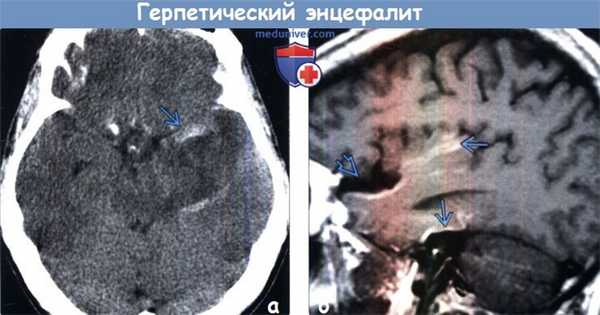

(а) Бесконтрастная КТ, аксиальный срез: у пациента 45 лет с лихорадкой и изменениями психического состояния в медиальном отделе правой височной доли определяется подозрительный участок слабого изменения плотности мозговой ткани.

(б) МРТ, Т2-ВИ, аксиальный срез: у того же пациента в медиальном отделе правой височной доли определяются изменения интенсивности сигнала. При исследовании СМЖ методом полимеразной цепной реакции (ПЦР) был выявлен ВПГ1. На ранних этапах течения герпетического энцефалита может сохраняться нормальная КТ-картина.